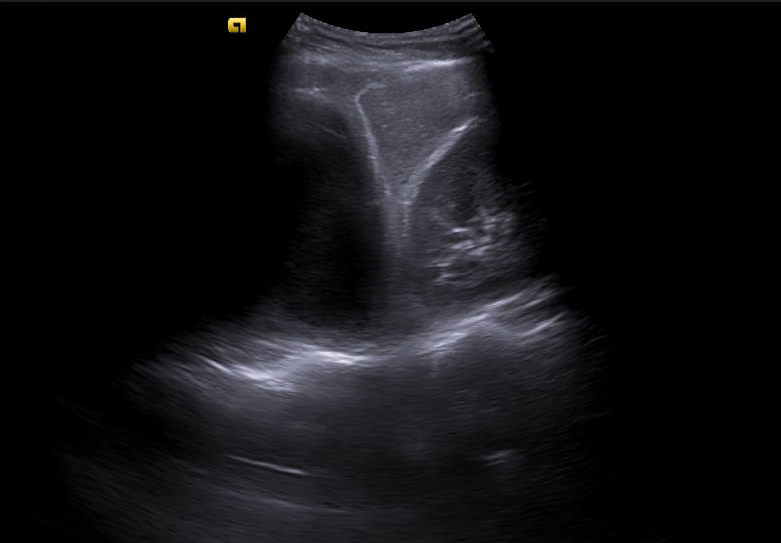

Realizamos ecografía clínica en la consulta objetivando un gran derrame pleural loculado de contenido ecogénico, con finos septos interiores y signo de la espina. Destaca que en el parénquima pulmonar no se observan datos de atelectasia, broncograma aéreo, consolidación ni hepatización, y apenas líneas B.